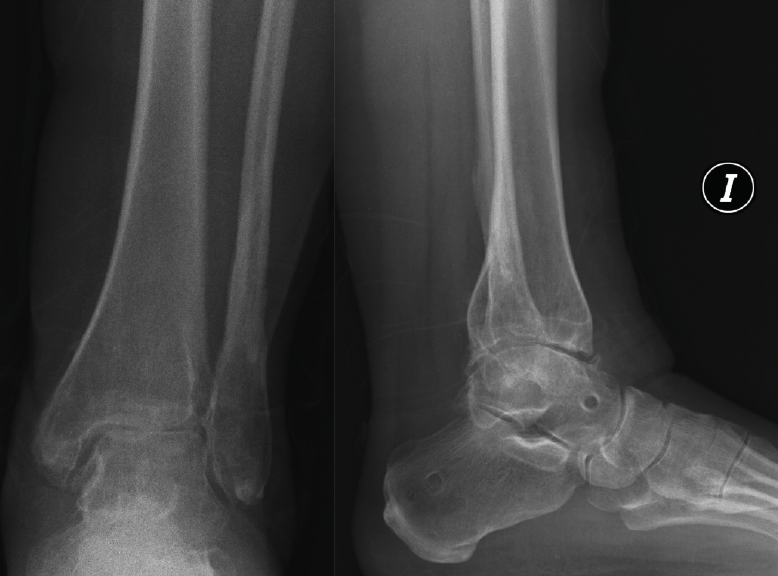

Figura 6. Artrosis postraumática de tobillo tras fractura bimaleolar hace 15 años.